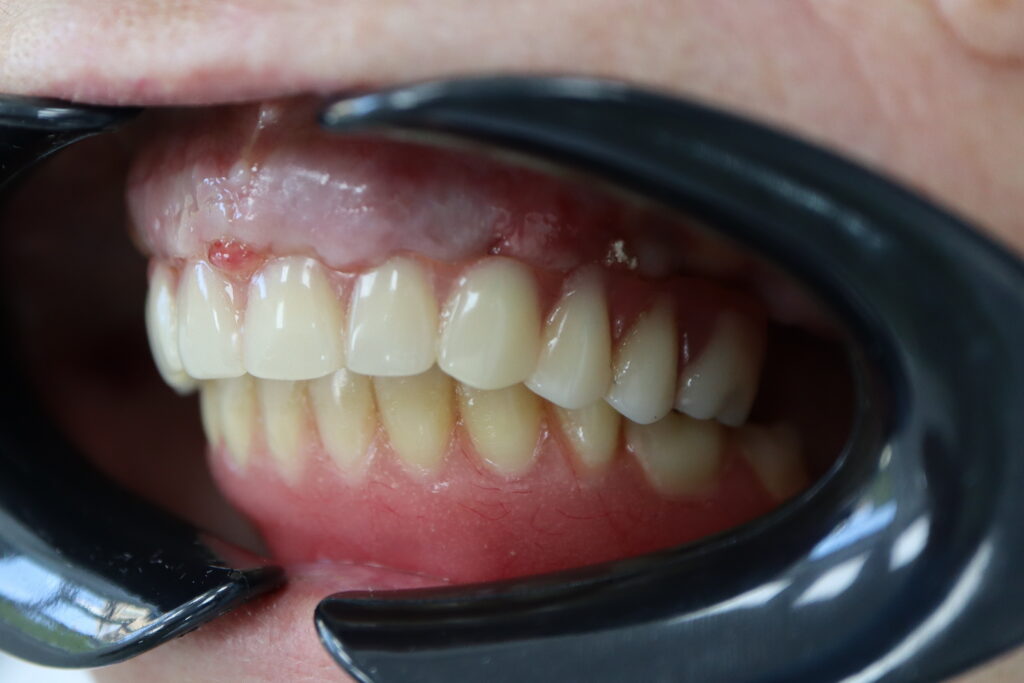

Спустя 7 дней на обеих челюстях зафиксированы металлоакриловые протез из 12 зубов.

Результат

Стоимость всего комплекса:

6400 USD (цена указана ориентировочно по курсу НБРБ на день оплаты)